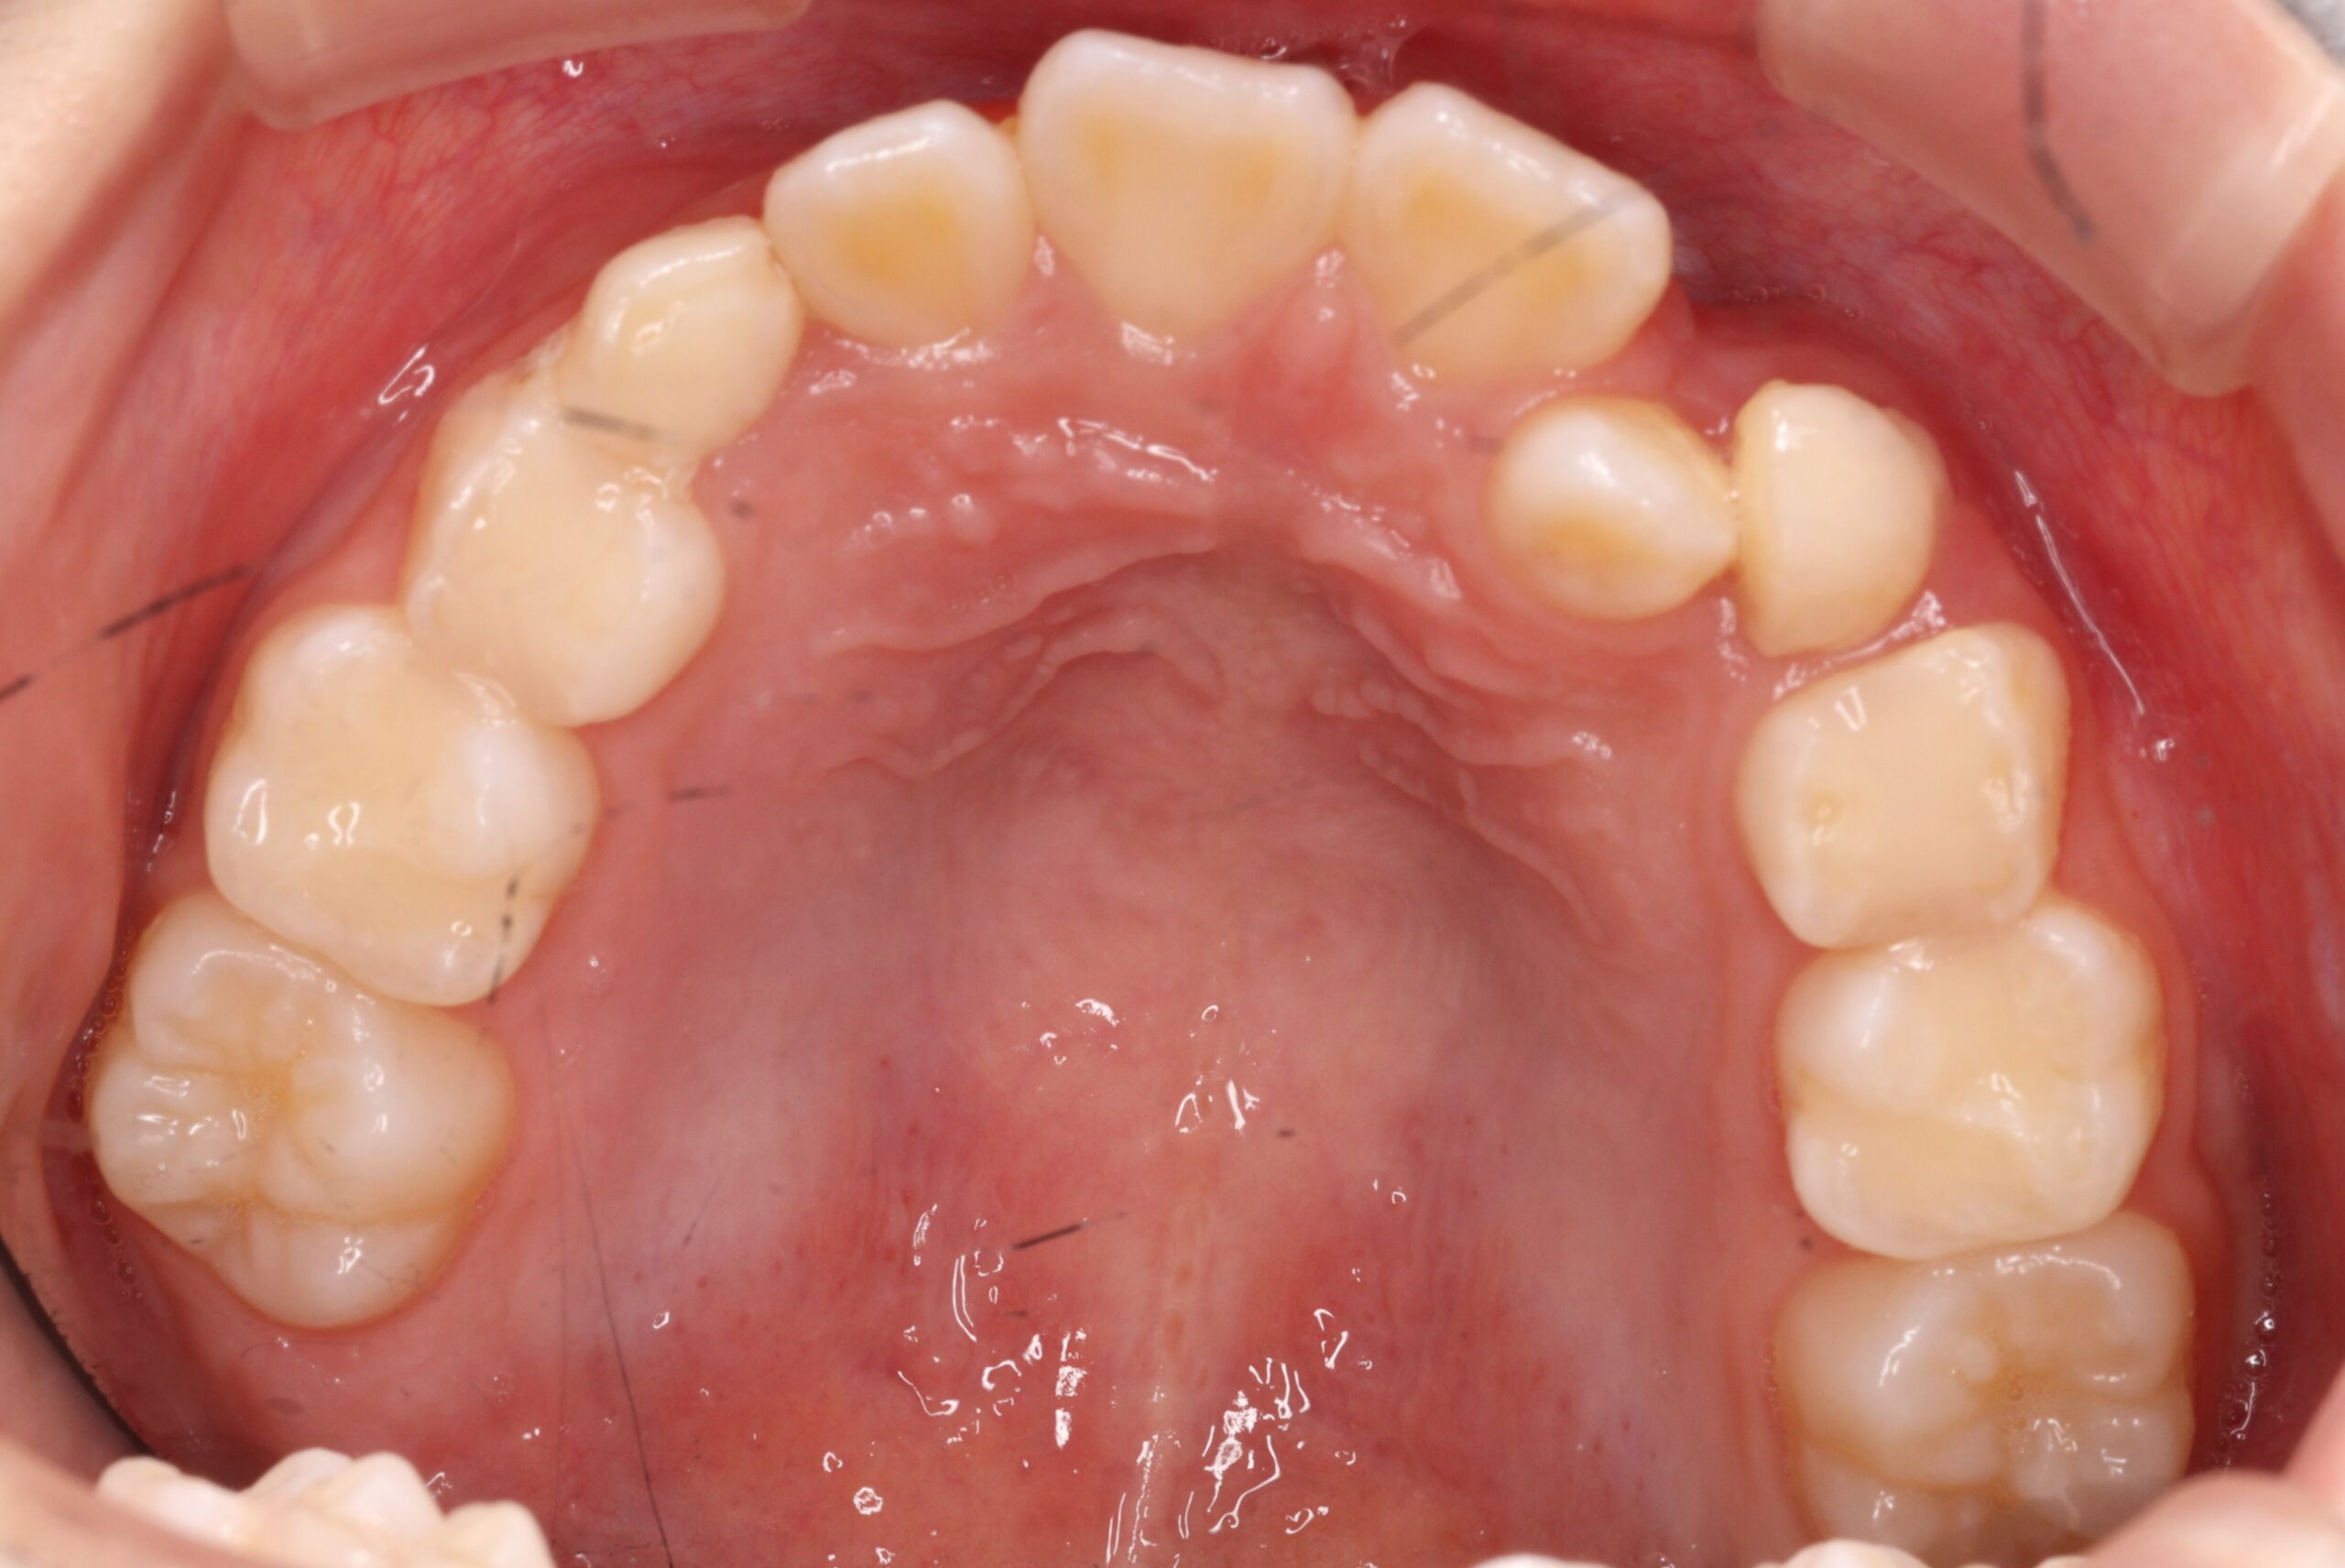

矯正術前:上顎

矯正術後:上顎